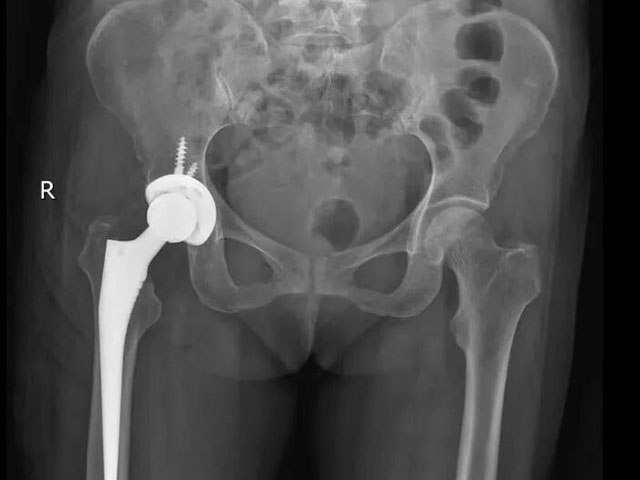

入科后,敖亮医生对王阿姨的病情进行全面研判:结合其年龄、骨折类型及身体基础状况,最终确定采用左全髋关节置换术。

“全髋关节置换术能直接替换受损的髋关节结构,术后患者疼痛缓解明显,可更快恢复行走功能,大幅缩短康复周期,尤其适合骨折移位明显、年龄较大的患者。”敖亮医生向王阿姨及家属详细说明手术方案及优势,获得了家属的认可。

手术过程中,敖亮医生精准操作,顺利为患者植入人工髋关节假体,确保假体位置与角度适宜,保障术后髋关节功能恢复。

术后患者影像资料